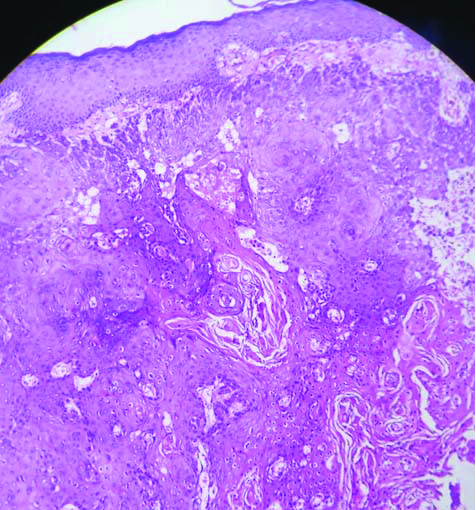

After a year of disease-free interval, he presented with enlarged left level V cervical neck nodes. An Fluorodeoxyglucose Positron Emission Tomography Contrast-enhanced Computed Tomography (FDG PET CECT) scan revealed this as the only site of disease; hence, he underwent completion radical neck dissection and was found to have infiltration of the sternocleidomastoid muscle, internal jugular vein, spinal accessory nerve, and surrounding muscles by the neck nodal mass. Histopathological review confirmed an SCC recurrence with extranodal extension. After four weeks, he presented with multiple umbilicated and tender skin nodules on the anterior aspect of the neck [Table/Fig-1]. Fine Needle Aspiration Cytology (FNAC) aspirated a light brown fluid of less than 0.5 mL. Smears revealed predominantly atypical squamous cells in a background of suppuration, favoring a diagnosis of SCC [Table/Fig-2]. An incisional biopsy was performed to confirm the diagnosis of SCC and to exclude the possibility of other primary cutaneous or appendage tumours and keratoacanthoma. Microscopy confirmed infiltrating SCC [Table/Fig-3]. He was started on palliative chemotherapy; however, the patient developed many similar nodules on the anterior and lateral sides of the neck [Table/Fig-4]. His general condition continues to deteriorate.

Skin with an infiltrating neoplasm composed of polygonal cells and areas of keratin pearls (H&E,100x).